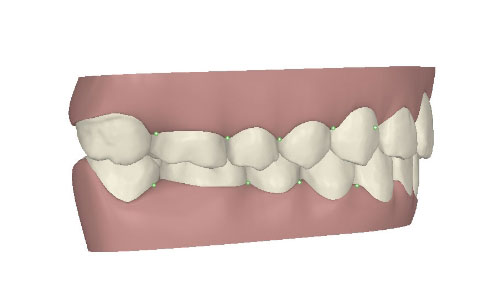

コンピューターを使って作製した透明なマウスピース型の矯正装置(アライナー)を段階的につけ替えていき、それにより歯列を矯正し、歯並びへと改善します。はじめに 治療開始から終了までのアライナーができあがってきます。マウスピース型矯正装置(インビザライン)の最大の特徴として「クリンチェック」というソフトがあります。3D のコンピュータ シュミレーション画像で、治療開始から完了までを目で見て確認することができます。

マウスピース型矯正装置(インビザライン)治療においては、クリンチェックというシミュレーションソフトを活用しております。

このクリンチェックの魅力は、治療前の現在の歯並びから治療後の歯並びを視覚化して患者様にご説明できる点にあります。

また、抜歯・非抜歯、全体矯正・部分矯正などそれぞれの治療パターンをシミュレーションすることが可能です。

アライナーとは、マウスピース型矯正装置で使用するマウスピース型の矯正装置のことです。ブラケット矯正は、曲げたワイヤーが戻ろうとする力を利用して歯を移動させます。対して、マウスピース型矯正装置は、 今の歯並びより少しだけ治療終了の歯並びに近いマウスピースを装着して歯に力をかけ、それを次々に付け替えていくことで歯を移動させます。治療終了までには数十個のマウスピース を使用することになります。